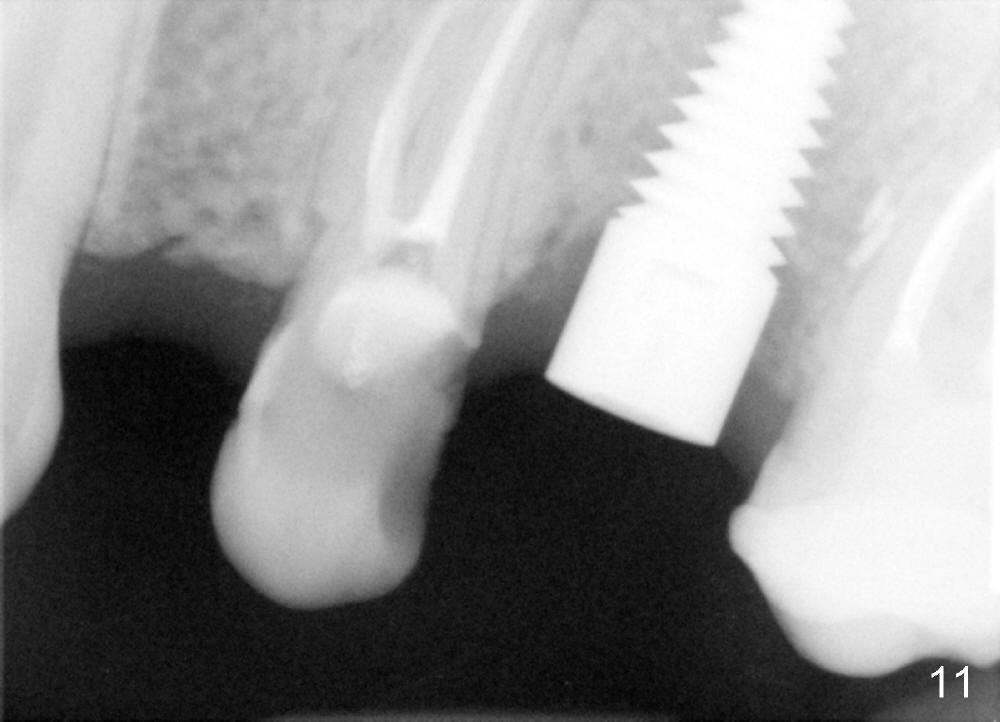

In addition to pain associated with dry socket, the buccal plate is atrophic 10 months post extraction (Fig.7 arrowheads, 1st case). A smaller implant (6x17 mm) is placed after bone expansion (Fig.8, bone appears to be soft). The buccal plate morphology improves immediately (Fig.9) and 6 days (Fig.10) post implantation and bone expansion. The patient returns for follow up 7 months postop; the implant appears to have osteointegrated (Fig.11). The implant has been restored for 3 months (09/11/2014).